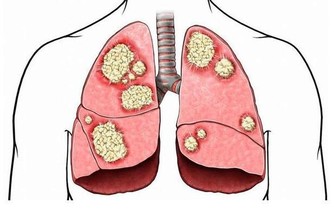

*****10、抽煙*****

抽煙的人以為尼古丁只會進入肺,殊不知,煙霧也會隨著消化道進入胃,直接刺激胃黏膜。引起黏膜下血管收縮、痙攣,胃黏膜缺血、缺氧,長此以往形成胃潰瘍。